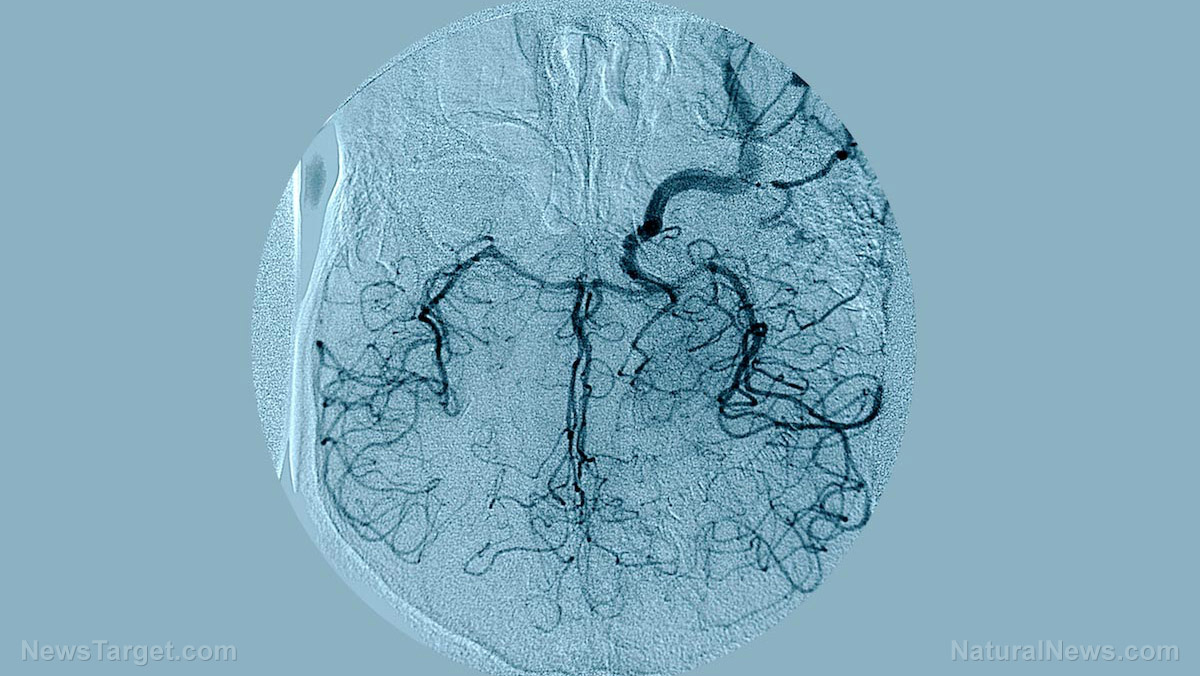

In a scene right out of a science fiction novel, scientists are now growing brains in a dish in an effort to further investigate mental health disorders. The "brains" are actually small three-dimensional spheroids containing model neural circuits, Independent.ie reports. The spheroids were grown from stem cells and developed through the same process that takes place in the womb.

According to the report, two spheroids were made, each measuring a miniscule 1/16th of an inch across. Each spheroid included a recreation of different areas of the forebrain, including the cerebral cortex, which is considered the most advanced part of the brain. The spheroids enabled scientists to view in real time some of the key events that occur in the brain during late-stage fetal development. In fact, the scientists have already managed to recreate the abnormal brain circuits of a fetus with Timothy syndrome, a rare birth defect that leads to heart problems, autism, epilepsy, and even death in early childhood. Through the spheroids, scientists were able to see where the defect occurred, and correct it with the use of two drugs.